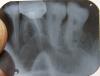

monplaisir Опубликовано 2 сентября, 2010 Поделиться Опубликовано 2 сентября, 2010 (изменено) Здравствуйте. Я недавно решила поменять железную коронку на металлокерамику, но внезапно этот зуб стал меня беспокоить, началось все с внезапной боли, которая усиливалась даже от малейшего касания зуба языком, неговоря уже о нажатиии и накусывании на него. Сделали снимок-врач сказала, что присутствует что-то похожее на гранулему.Так ли это? И какое лечение здесь будет эффективно? Изменено 2 сентября, 2010 пользователем monplaisir Ссылка на комментарий

x3m Опубликовано 3 сентября, 2010 Поделиться Опубликовано 3 сентября, 2010 Так ли это? И какое лечение здесь будет эффективно?это так.лечение - распломбировка трех корневых каналов, поиск четвертого и пломбировка всех четырех(!) каналов.далее - ВКВ+коронка (поищите по форуму, что это) кстати, пятый зуб - так же лечить (перелечивание каналов, ВКВ+коронка) Ссылка на комментарий